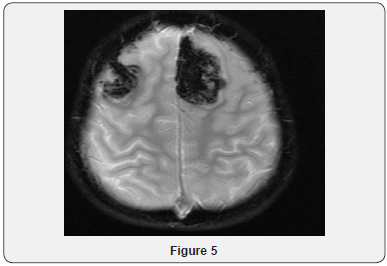

Echocardiogram Holter monitor and Eye examination all were normal. The patient underwent muscle biopsy which showed mild lipid myopathy with type 2 muscle fiber atrophy, but with no morphological evidence of mitochondrial disease. A stat CT brain showed hemorrhagic infarction and some fresh bleeding in subarachnoid space (not older than 3 days), possibly on the basis of ischemic lesions, considering the further hypodense lesions in the parasagittal area on bi-occipital and parieto-occipital regions, more extended on the left side (Figure 4). The neurosurgery team was notified, but it was determined that the patient has poor prognosis and is not candidate for surgery. Gradually, the patient developed respiratory distress and was transferred to the intensive care unit and required mechanical ventilation. He was monitored continuously by EEG. At that time, he showed subclinical seizures originating from the posterior head region, right side more than left. A burst suppression pattern was established, but during the burst period he was having multifocal spikes and polyspikes. Brain MRI showed massive hemorrhagic infarction of non-vascular distribution pattern involving the posterior occipito-parietal, region with brain stem area and cerebellum (Figures 5-9) and a lesion extending to the temporo-parietal region (Figures 5,7). Cerebral angiography showed multiple territorial hemorrhagic infarctions, with no blood entering intracranially in a case of massive intracranial edema, suggesting brain death (Figure 10). Using homozygosity mapping followed by whole exome sequencing, we identified a homozygous mutation of APOA1BP that caused lethal infantile leukoencephalopathy. The patient continued to deteriorate, then died at the age of four years.